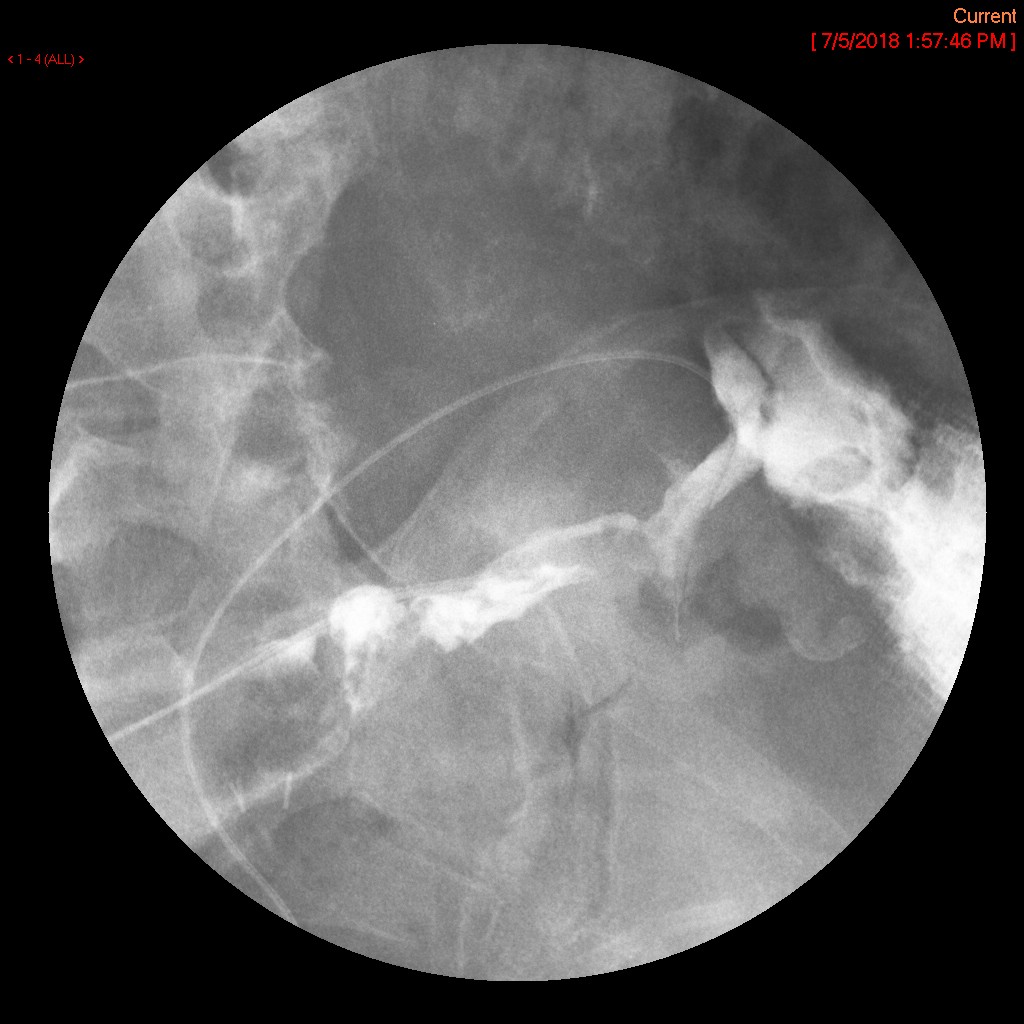

- The gynecologist will begin injecting contrast material into the uterus. Obtain images periodically throughout the procedure (usually at the direction of the gynecologist). The images should include the uterine cavity filled with contrast material, bilateral fallopian tubes filled with contrast material, and spillage and dispersion of contrast material into the peritoneal cavity (image 1) (image 2) (image 3) (image 4) (image 5).